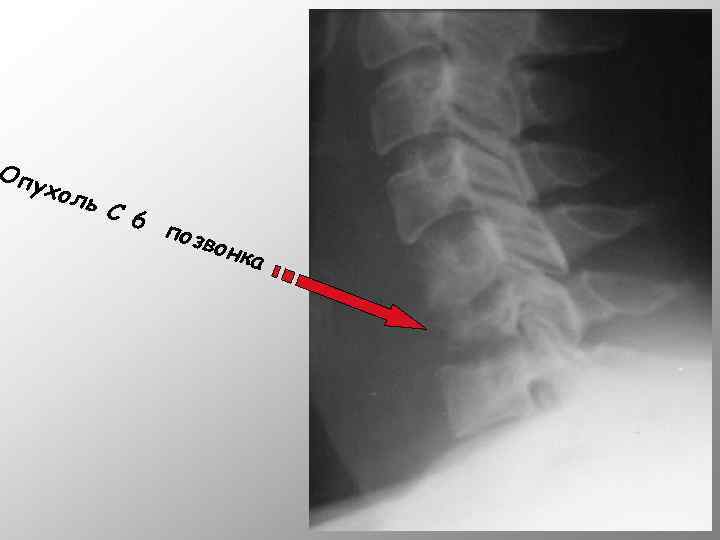

Опу хол ь C 6 п озво нка